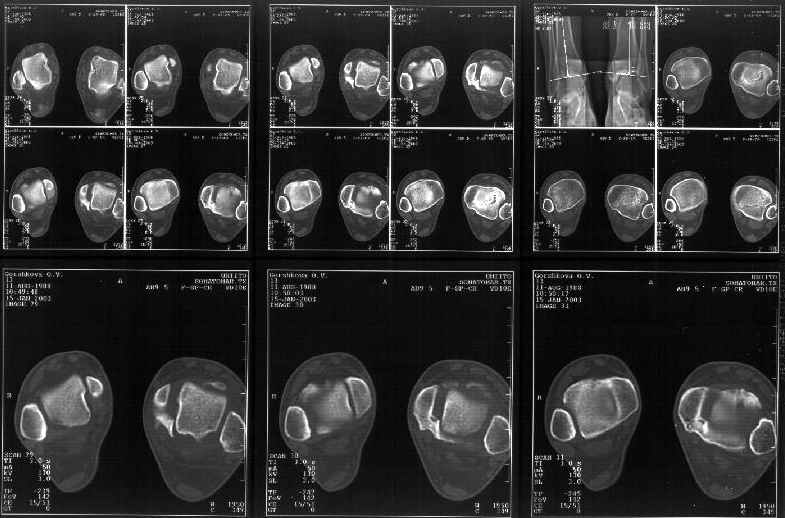

На следующий день пациентке сделали КТ. Может быть, после просмотра картинки будут другие предложения? Не убрать ли ве-таки этот фрагмент

позади внутренней лодыжки, который оттесняет таран кнаружи?

Здесь 4 среза, начиная от основания лодыжки и проксимальнее. Где, по Вашему мнению, проходит линия перелома, отделяющая переднюю часть внутренней лодыжки от большеберцовой кости? Заранее спасибо.

Я пометил линию перелома черной линией.

К сожалению на последних присланных срезах КТ нет более низкого, через таран, среза, который был на прежнем майле. На XR я попытался показать

стержень внутри сустава и то как он раскрывает пространство между тараном и мед. малеолом.

Сегодня пациентке сделали сравнительную КТ. А ксиальные и Фронтальные срезы приложены. Ваше мнение?

Фронтальные

Аксиальные

На КТ я попытался изобразить скромными своими способностями (А)- место перелома, (С)- нормальный суставной зазор меж тараном и тремя его маллеолами. (В)- образовавшийся в результате перелома широкий раза в три зазор, позволяющий, по-моему, сублюксацию тарана при ходьбе. В свете данных КТ, критически важных, я бы предложил вертикальную остеотомию места перелома

задне-внутренним подходом и фиксацию мед. маллеола прижатым к тарану с помощью тонкого compression screw. После этого гипсовый сапожок и немедленное расхаживание ноги.